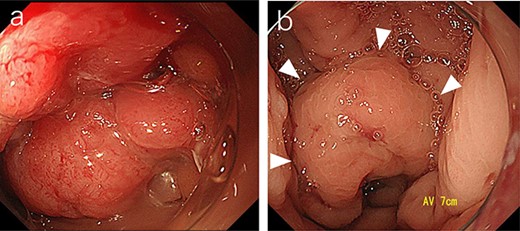

Subsequently, we performed transrectal drainage of the abscess in the lithotomy position without endoscopy. After the incision of the excluded rectal mucosa at 7 cm from the anal verge by the electric scalpel and penetration of the abscess wall by the Kelly clamp, a massive purulent discharge was observed. Next, a transanal rectal drainage tube (MIT drain®, effective length 12 cm; Create Medic Co., Ltd, Yokohama, Japan) was inserted into the abscess cavity without the use of a guide wire, and saline irrigation was performed. After transrectal drainage, the patient’s pain and inflammatory laboratory findings improved rapidly. Pelvic CT showed shrinkage of the cavity 3 days after the drainage (Fig. 3). Bacterial culture test and cytology of the drainage contents revealed negative growth and no malignancy, respectively. The biopsy results showed moderately differentiated tubular adenocarcinoma. The inserted tube was removed on the seventh day after the drainage, and the patient was discharged on the eighth day. In the outpatient department, total colonoscopy revealed that the exclusion from outside the rectal wall on the anal side of the tumor diminished, and the incised mucosa healed as a scar. Ink sticks were marked near the scar on behalf of the combined resection of the tumor. Pelvic CT revealed that the pelvic abscess had disappeared 1 month after drainage (Fig. 4).

Pelvic CT performed 3 days after drainage in the sagittal section. Abscess cavity remarkably shrunk (arrowheads).